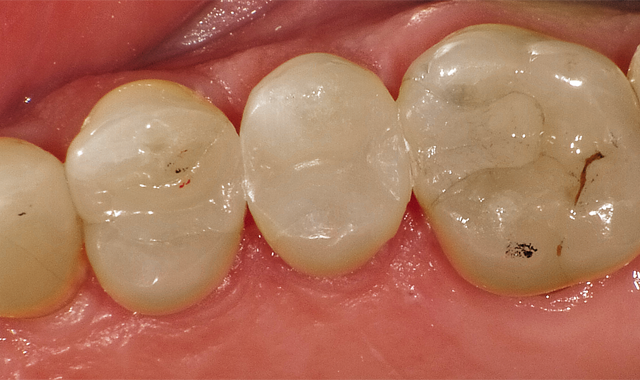

This case involved replacing a chipped Class IV on number 10 (Fig. 4).

Case 2 involved replacing a chipped Class IV on No. 10.

The beauty of the G-ænial Sculpt system is that one can get a superior chameleon effect from using a core shade (A2, for example) but in the case presented, we simply layered an A2O, then an A1 and then AE (adult enamel) over the very outer layer.

The first layer of A2O was placed on the lingual surface after etching and bonding (Fig. 5).

The first layer of A20 is placed on the lingual surface after etching and bonding.

The key here is looking from the incisal room and leaving enough room to blend in your A1 or A2 body shade and then if you want, placement of Adult Enamel.